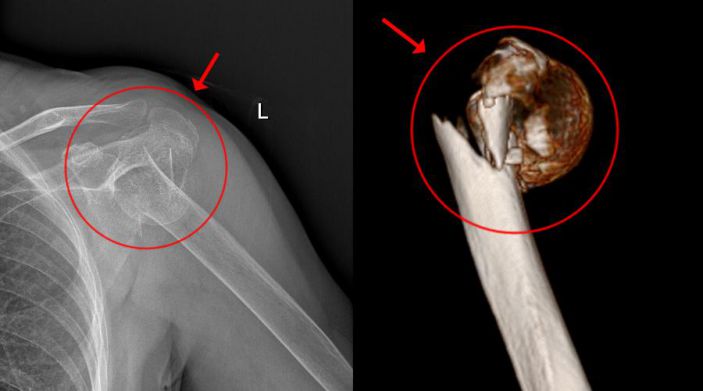

經CT檢查發現,患者的左肱骨上段粉碎性骨折,骨盆左恥骨上下肢骨折。此外,老太太還伴有老年性骨質疏松、雙側頸動脈明顯粥樣硬化、高血壓病、高脂血症等疾病。

骨科主任吳志斌考慮到患者骨盆左恥骨骨折未有明顯移位,可行保守治療,而左肱骨上段粉碎性骨折,需待患者病情穩定、可耐受手術後,行肩關節置換術。患者家屬表示願意配合一切治療。

吳主任根據CT+三維重建先行拟訂詳細的手術方案。9月4日在經過充分的術前準備後,老太太被送進了層流淨化手術室,行左側人工肱骨頭置換術。家屬在手術室外焦急地等待,而此時手術室内的吳志斌主任在麻醉科的配合下,根據方案有條不紊地開展手術,娴熟地取出左肱骨頭,并給予安裝肱骨假體,考慮到患者骨質疏松明顯,吳主任還特地加用了骨水泥。術中老太太未出現血壓下降及意識改變等其他不适,整個手術非常順利,再次給患者家屬滿意的答卷。經過醫護人員的對症治療、精心護理,老太太将于近日康複出院。

△術前